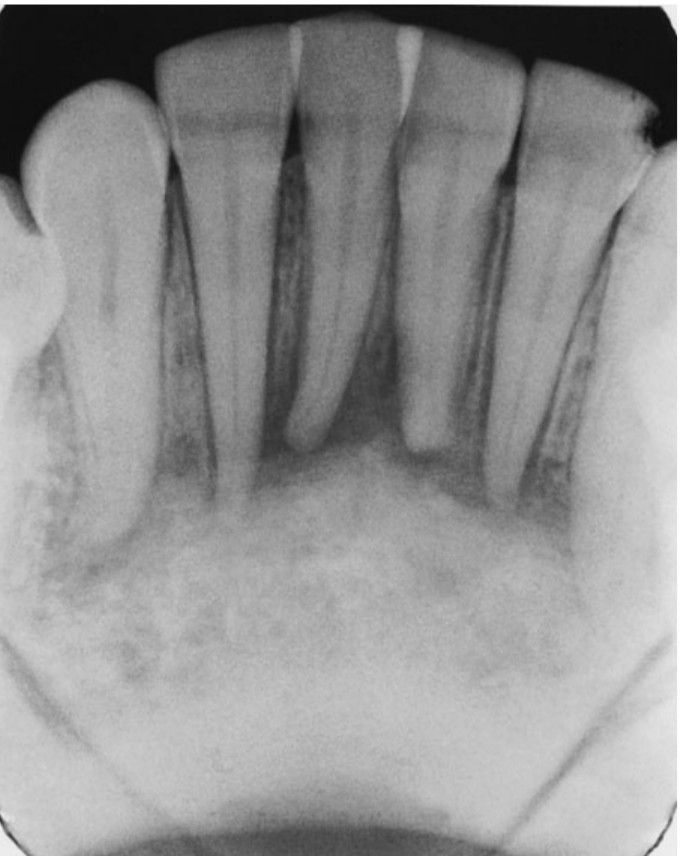

Periapical radiograph demonstrating an irregular radiolucency involving the bone of the apical region of the mandibular anterior teeth, without change in root anatomy. The teeth tested vital. The radiographic finding was the first indication of involvement of the boney adenocarcinoma.